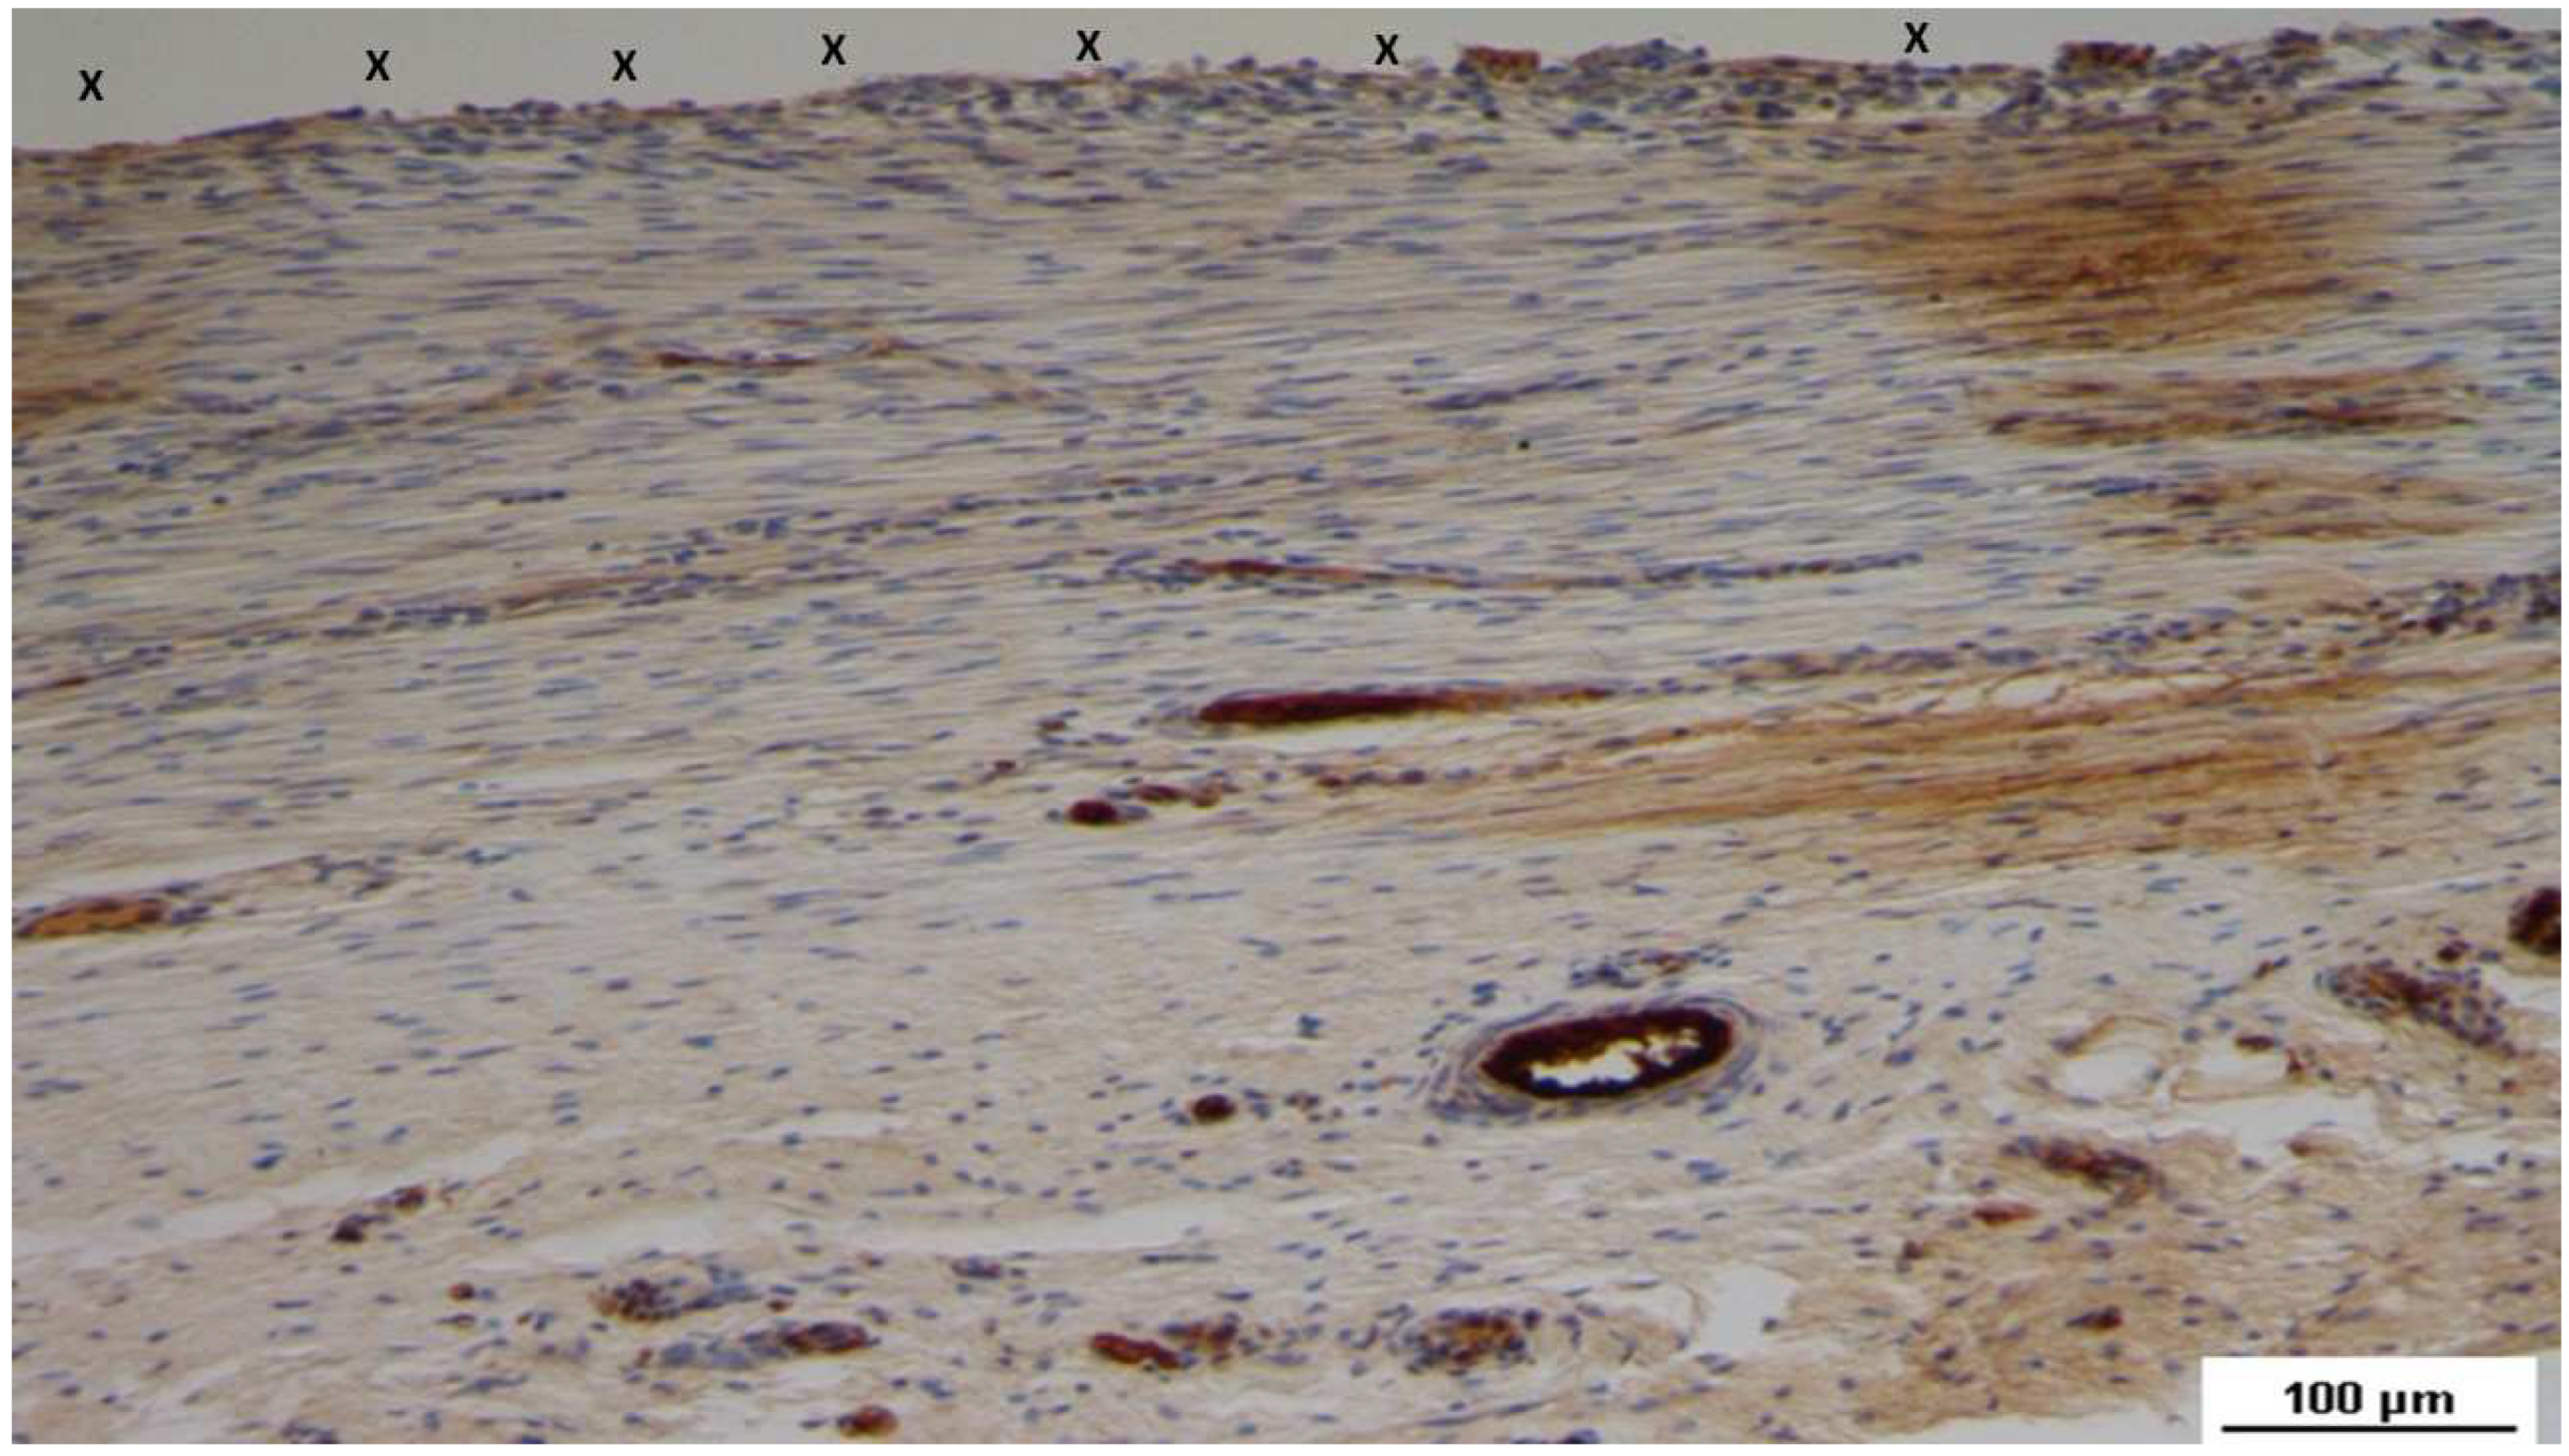

Figure 10. Biopsy specimen excised 4 months post-implantation (Midterm – MT). A venous structure (yellow arrows) showing smooth muscle development, induced by SMA, is seen near the 3D scaffold (X). SMA 50X.